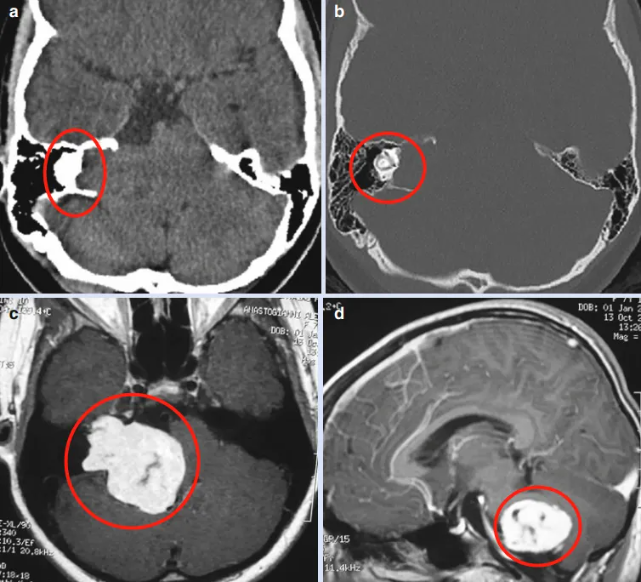

医院的检查结果也吓了父母一大跳,原来Elsa已经患上严重的右侧听觉障碍和凝视性眼震,并伴有严重的共济失调。CT和MR检查显示,这一切的“罪魁祸首”是一个位于CPA区,甚至“截断”脑干的巨大肿瘤占位,初步诊断为听神经瘤。

术前CT和MR显示CPA区(桥小脑角区)有巨大均匀强化的肿瘤,病变向前上方延伸至颅中窝硬膜,向前内侧延伸至颈动脉岩段,尾侧至颈静脉孔。颞骨岩部严重受压迫损伤,脑干明显受压迫,但无脑积水,未检测到NF2的临床症状或放射学体征。